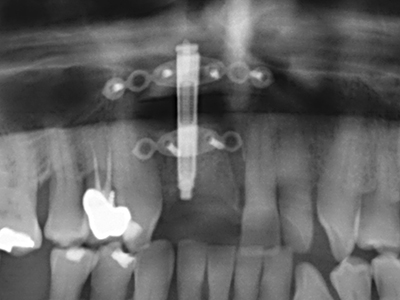

Preparation of the lateral window during an external sinus floor elevation is challenging, particularly for implantologists with little surgical experience. Removal of the bone cover of the sinus without injuring the underlying Schneiderian membrane is only part of the operation – after establishing an adequate access, the membranous lining of the sinus must be carefully mobilized to make space for the augmentation materials or the implants. Piezo surgery is useful for this indication in two ways: diamond-coated instruments can be used for selective bone ablation and the underlying mucous membrane remains intact when the procedure is done carefully. The ultrasonic frequencies also enable detachment of the mucous membrane without complications – the frequencies are transmitted into the space between the mucous membrane and sinus floor by special blunt attachments (Cassetta, Ricci et al. 2012, Pereira, Gealh et al. 2014) (Rickert, Vissink et al. 2013). As a result, it is not surprising that current reviews of external sinus floor elevation positively evaluate the use of piezoelectric devices as well as the use of roughened implant surfaces and bone replacement materials (Wallace, Tarnow et al. 2012).